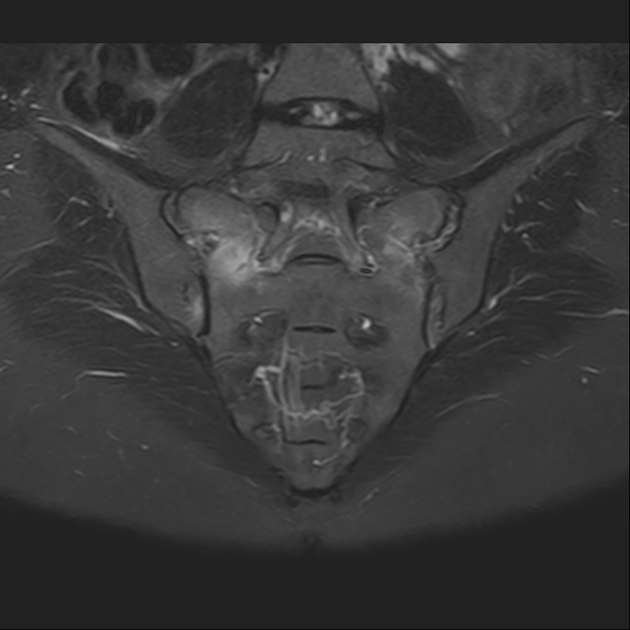

磁共振检查:

STIR

6、磁共振上可以发现骨折线周边明显的骨髓水肿,增强扫描明显强化

磁共振影像表现